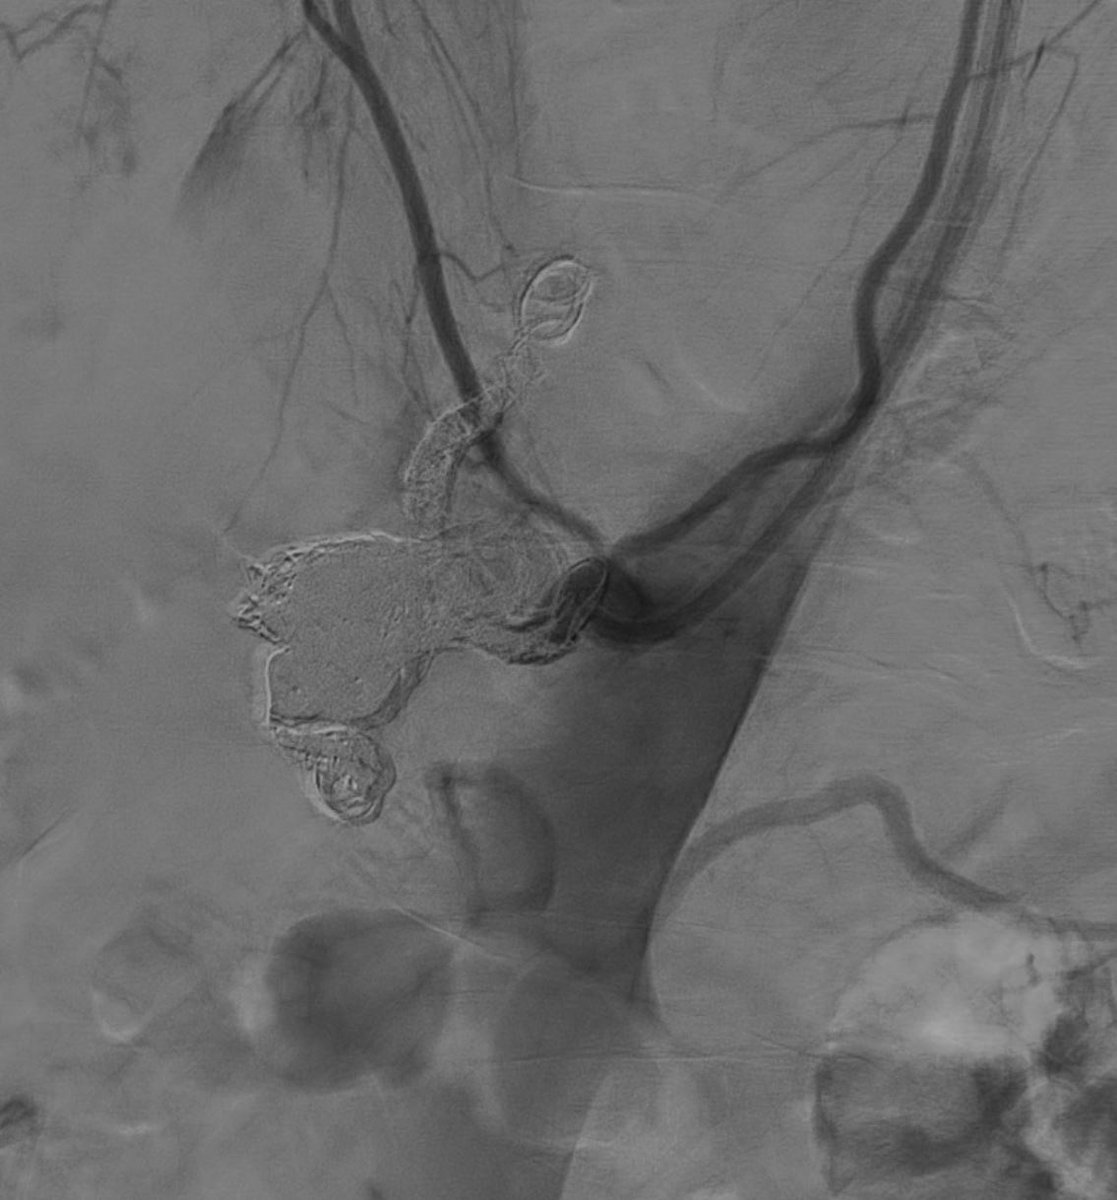

Live

@MountSinaiIR 2.5cm celiac artery aneurysm status post coils with 21#InterlockCoils into the aneurysm and proximal branches with no more flow. Post-embolization SMA run shows collateral filling of celiac branches#IRAD#radrespic.twitter.com/cD6Y7d7Ilx